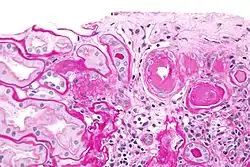

![]() صورة مجهرية تظهر التزجج الشرياني [الإنجليزية] الكلوي (الحلقة الوردية يمين الوسط). الصورة محضرة بصبغة باس. صورة مجهرية تظهر التزجج الشرياني [الإنجليزية] الكلوي (الحلقة الوردية يمين الوسط). الصورة محضرة بصبغة باس. | |

في الكليتين، كنتيجة لفرط ضغط الدم الشرياني الحميد، يتراكم الهيالين (مادة وردية اللون متجانسة عديمة الشكل) في جدران الشرينات والشرايين الصغيرة ما يؤدي إلى زيادة ثخانة جدرانها وتضيق لمعات الشرايين، وهي عملية تدعى بالتصلب الشريني. يؤدي نقص تدفق الدم الناتج عن ذلك إلى حدوث ضمور نبيبي، وتليف خلالي، وتبدلات كبيبية (كبيبات أصغر فيها درجات مختلفة من توضع الهيالين- من الخفيف وحتى تصلب الكبيبات)، وتندّب في المنطقة المحيطة بالكبيبات (تليف حول كبيبي). في المراحل المتقدمة، سيحدث القصور الكلوي. تكون الوحدات الكلوية (الكليونات) الوظيفية ذات نبيبات متوسعة،[4] وغالبًا ما توجد أسطوانات هيالينية في لمعة النبيبات. تشمل الاختلاطات الإضافية التي غالبًا ما تكون مرتبطة بحدوث الاعتلال الكلوي بفرط الضغط الأذية الكبيبية التي تؤدي إلى ضياع البروتين والدم مع البول.